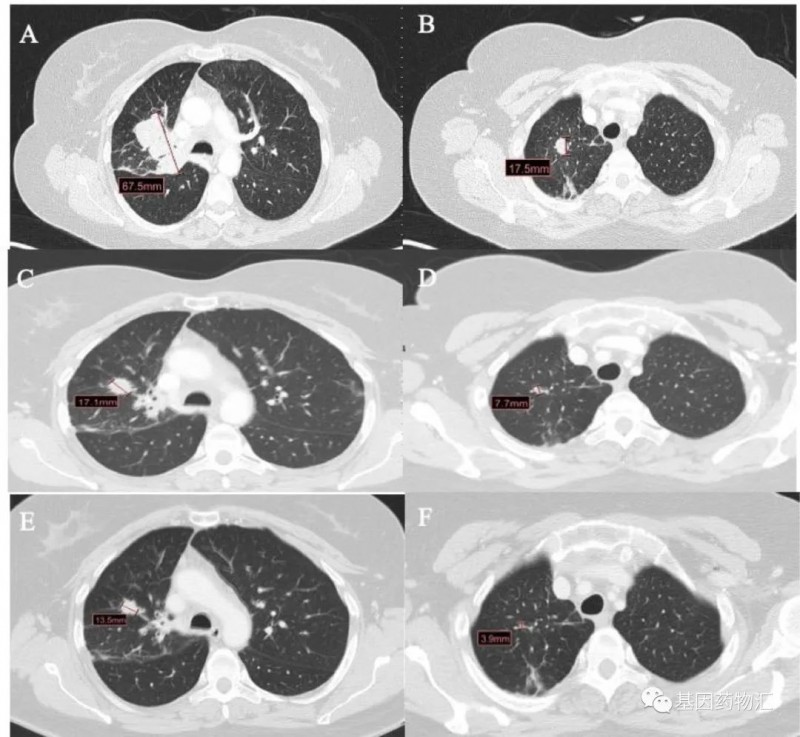

一位49岁的女性患者,罹患Ⅳ期肺腺癌,且测试存在EGFR ex20ins阳性,为EGFR P772_H773insPNP和TP53共突变。

患者从2018年7月开始接受卡铂+培美曲塞治疗,4个周期后继续使用培美曲塞维持治疗1年。至2019年7月患者复查CT时发现肺部和淋巴结进展,于是接受了Amivantamab(JNJ-6372,JNJ-61186372)的治疗,再次达到临床缓解,持续了9个月。

至2020年5月,患者出现了严重的背痛症状,CT检查显示骨骼与淋巴结进展。患者接受了姑息性放疗,以及多西他赛+尼达尼布(Nintedanib)方案治疗,但提示了疾病进展。

此后患者接受了Mobocertinib(TAK-788)的临床试验,达到了临床缓解,症状显著改善。至结果发布时,患者的疗效已经持续了超过8个月。